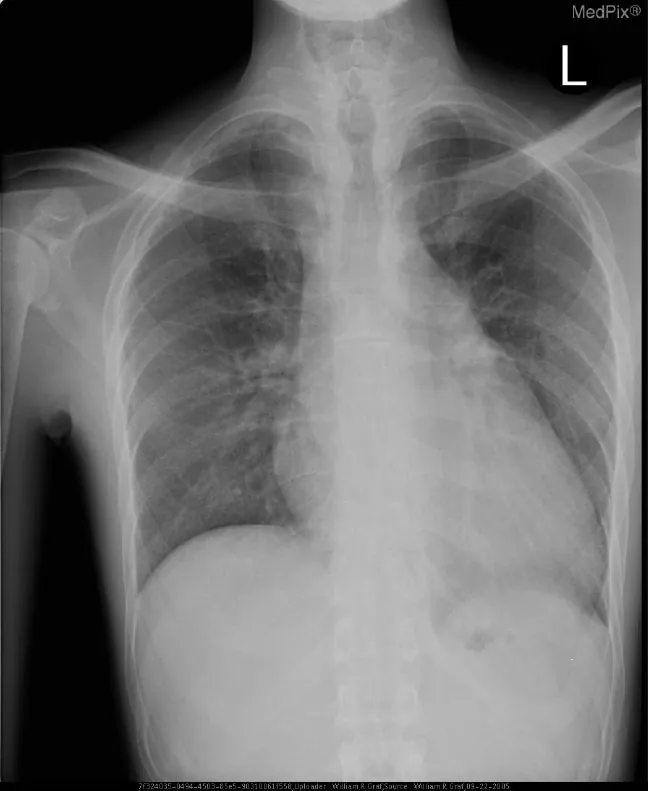

With a new diagnosis of HF, the suspicion of coronary artery disease is high and must be investigated. More invasive testing, such as percutaneous coronary intervention, can further confirm coronary artery blockage as causation. This procedure is an invasive procedure in which a catheter is threaded through the femoral artery, dye is injected, and coronary blockages can be detected through this dye. If the patient is experiencing an acute exacerbation of HF, chest X-rays assist with identifying pulmonary edema or cardiomegaly, which means ventricular enlargement to accommodate excess fluid (Figure 12.20). While diagnostic imaging is expansive in the work up of HF, other laboratory values assist with determining disease severity.

X-ray showing ventricular enlargement with apex of heart taking up right side field.

Figure 12.20 Due to enlargement, the apex of the heart is taking up the right-side field (the patient’s left lung). (credit: “Graves Disease” by Naval Medical Center Portsmouth: William R Graf/National Library of Medicine, Public Domain)